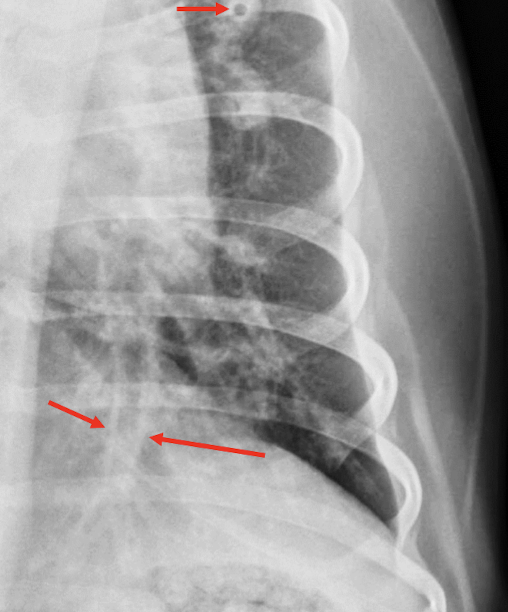

Lung Pattern?

Pneumothorax *Arrows = atelectasis*